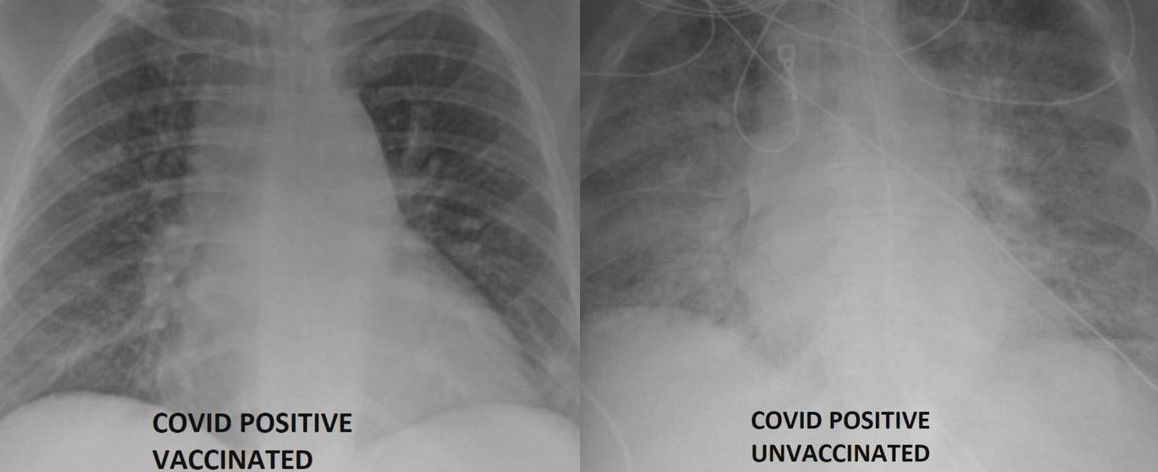

Jeden z amerykańskich lekarzy zajmujących się pacjentami z COVID-19 opublikował zdjęcia rentgenowskie chorych pacjentów. Na jednym z nich widać płuca osoby zaszczepionej, a na drugim płuca osoby, która nie przyjęła szczepionki.

Lekarz udostępnił dwa zdjęcia rentgenowskie płuc zakażonych koronawirusem. Jeden z pacjentów był zaszczepiony, a drugi nie. Różnica w przebiegu choroby jest kolosalna.

Dr Ghassan Kamel pracuje SSM Health Saint Louis University Hospital w Missouri i od marca ubiegłego roku zajmuje się chorymi na COVID-19. Aby zachęcić do szczepień, pokazał zdjęcia chorych płuc i jaki wpływ ma na nie szczepionka.

Na zdjęciu rentgenowskim chorego, ale zaszczepionego pacjenta nie widać żadnych niepokojących zmian w płucach. Natomiast u zakażonej, ale niezaszczepionej osoby płuca są zabielone. Lekarz wyjaśnia, że to zmętnienie płuc, czyli zacienienia typu mlecznego szkła widoczne dopiero na skanach tomografu komputerowego.

Zmętnienia płuc wskazują zwykle, że płuca są wypełnione np. płynem. To może nie tylko utrudniać oddychanie, ale także prowadzić do poważniejszych schorzeń.

Doktor Kamel powiedział, że osoby ze zmętnieniem płuc, częściej potrzebują pomocy medycznej. Częściej trafiają na oddział intensywnej terapii i wymagają podłączenia do respiratora. Lekarz dodał, że prawdopodobnie gdyby zaszczepiona osoba trafiła do szpitala nie potrzebowałaby takiego leczenia.

Mogą wymagać respiratora lub zostać zaintubowani i zasadniczo podtrzymywania życia. Jeśli nie lubisz nosić maski to z pewnością nie spodoba ci się respirator – powiedział Kamel dla stacji KSDK.